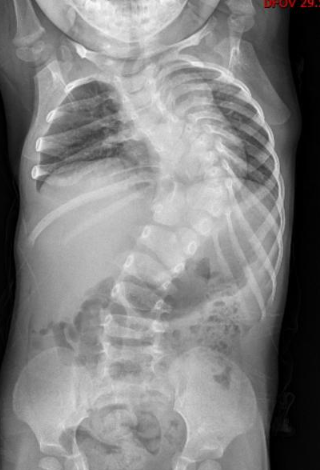

可可(化名)今年 12 岁,家住新洲。从一出生起,她就患有先天性椎体发育畸形,脊柱向左倾斜,身体扭曲。2 岁时,可可脊柱倾斜度数达到了 90 度,上半身几乎被「折」成了直角。父母带可可四处求医,可都因为畸形严重且复杂,矫形难度大,年龄小且治疗周期长,未来治疗存在不可预测性,迟迟没能得到有效救治。

「如果把脊椎比作一栋大厦,她从第 5 胸椎到第 3 腰椎如同一片『废墟』,有的『楼层』合并,有的被拆成两半,没有一处正常。」武汉儿童医院骨科副主任医师周治国当时在北京进修,接诊可可后,联手北京的专家为可可进行检查。

令他担忧的是,当时可可年仅 2 岁半,是生长发育的快速生长期,这样严重的结构畸形将导致胸腔空间减少,直接压迫脏器。对于可可来说,矫正手术必须得做,而且要尽快。

2015 年,2 岁半的可可在武汉儿童医院接受了一期手术,专家在她的胸椎、腰椎植入 4 根生长棒和 8 枚椎弓根钉当「支架」,尽可能给扭曲的脊柱以支撑,延缓侧弯的进展,同时为胸腔和内脏争取生长空间。